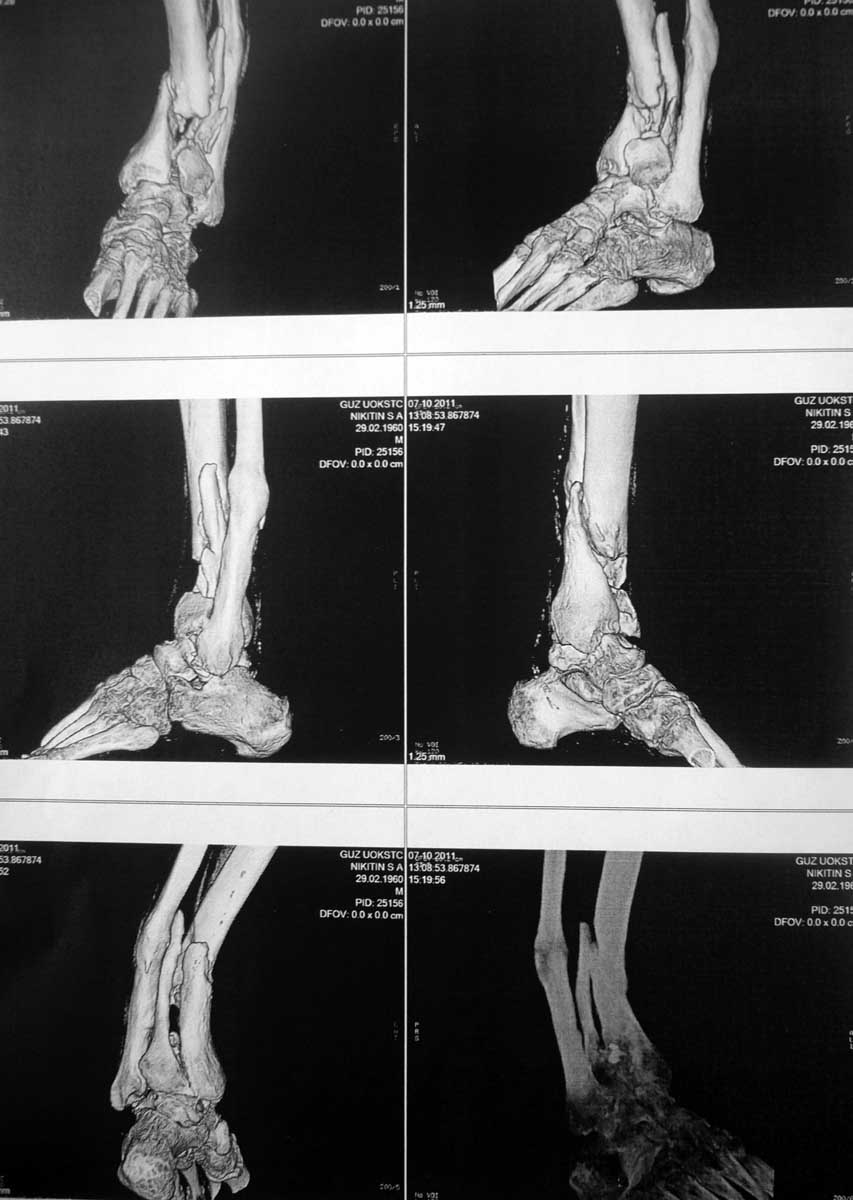

Для определения деформации длинных костей полезны обычные рентген снимки, а 3D снимки, оставаясь красивой картиной снаружи, не дают полную информацию про то, что внутри сустава. В дальнейшем необходимость исследования на КТ будет, но для выработки тактики помогут поперечные и сагиттальные срезы. На всю конечность длинные снимки помогут сделать расчет угла деформации, и прицельный снимок голеностопа оценит сустав.

На 3D снимке виден большой фрагмент в переднем отделе, а поперечные КТ срезы уточнят точную топографию фрагментов. Возможно, основной фрагмент только спереди, и реконструкцию можно делать из переднего доступа с артротомией. Любая передняя длинная пластина (предпочитаем DePuy) с костным графтом и коррекция малоберцовой из латерального доступа. Тенденцию варуса можно устранить временным на три недели медиальным наружным фиксатором со стержнями в пятке и голени.

Мне кажется, что серьёзно рассчитывать па восстановление функции голеностопного сустава после перелома пилона Ruedi III не леченного должным образом в течение двух лет, не приходится. Сустав погиб.Можно предположить данные КТ – полностью разрушенные переднелатеральную и латеральную части суставной поверхности большеберцовой кости, что типично для переломов пилона из-за вальгусной установки пяточной кости. Но они будут иметь ценность, только если решиться на реконструкцию голеностопного сустава. Выделить из рубцов смещённые, сросшиеся в неправильном положении между собой мелкие костные отломки с суставной поверхностью, выполнить реконструкцию суставной поверхности пилона, выполнить надёжный остеосинтез порозных костей – это техническая задача, с моей точки зрения, не имеет решения. Кроме того, всегда приходиться помнить об угрозе самого тяжёлого и нередкого осложнения применения накостного остеосинтеза при переломах пилона – нагноениях. Если результат с большой степенью вероятности заранее известен, стоит ли выполнять реконструкцию? И ещё. Возможно, для хирурга и не имеет принципиального значения, чем выполнять артродез. Для больного, который в течение двух лет не мог наступать на ногу, возможность нагружать ногу после операции трудно переоценить. Поэтому преимущество артодеза стержнем, мне кажется, очевидны.